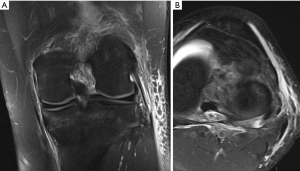

The symptomatology of LCL injury includes swelling, lateral joint line pain, difficulty ascending and descending stairs, and problems with cutting or pivoting. Patients classically ambulate with knee hyperextension or have a varus thrust gait. Lateral joint line tenderness also can occur and patients typically have opening with varus stress at 30 degrees of knee flexion. If there is varus instability at both 0 and 30 degrees, concomitant ACL and/or PCL injury is likely. If patients have increased tibial external rotation at 30 degrees, a combined LCL and PLC injury is probable. A careful neurovascular exam is important, as common peroneal nerve injuries can occur. Grading of the LCL as well as the PLC are quantified by the amount of lateral gapping with varus stress where grade I is defined at 0–5 mm opening, grade II is 5–10 mm, and grade III is >10 mm. Grade I and II indicate a partial tear, while grade III represents a complete tear. Radiographic analysis includes AP, lateral, and varus stress views while MRI is the imaging method of choice to provide information on the location and severity of the soft tissue injury (Figure 2) (7). Although posteromedial in anatomic location, interest in the posteromedial capsular attachment to the medial meniscus has grown, as a tear here, coined a ramp lesion, has been shown to possibly impart important rotational stability as well (Figure 3) (8). With injury to the PLC, meniscocapsular separation medially can occur and also should be investigated. Currently, no physical examination has been found to be sensitive or specific in diagnosing ramp lesions.

Figure 2 Coronal (A) and axial (B) MRI showing injury to the lateral collateral ligament (LCL).

Initial imaging should involve standard radiographs, which are generally unremarkable. However, one should carefully evaluate for a Segond fracture, which is pathognomonic for an ACL tear. This occurs secondary an anterolateral (AL) capsule avulsion from the proximal lateral tibia (Figure 1). An MRI is recommended for evaluation for an ACL tear, meniscal tears, subchondral damage, loose bodies, and bone bruising (Figure 5), which, according to some studies, can all serve as pain generators. Bone bruising occurs in the lateral compartment in over 80% of ACL ruptures, while the medial compartment is involved in varying percentages (14). The literature is conflicting regarding whether these bone bruises are a source of knee pain. This bruising is thought to occur from the tibia and femur impacting one another during a shifting moment. Typically, this occurs in the middle 1/3 of the lateral femoral condyle as well as the posterior 1/3 of the lateral tibial plateau. In two studies, the only factors shown to be linked to bone bruising are injury during non-jumping activities and younger patients (15,16). The severity of bruising has been thought to be related to the amount of impact and possibly future knee function. Chondrocyte damage has been seen histologically with bone bruising and chondral surface thinning in the area of bruising between 1 to 6 years after injury (17,18). With 12-year follow-up in one of these studies, bone bruise changes resolved and there was no difference in pain (16). One study of 672 patients undergoing ACL reconstruction did not link knee pain or symptoms to a bone bruise at index ACL reconstruction, but did link BMI, older age, female sex, LCL injury, MCL injury, medial meniscus status, lateral meniscus status, laxity on Lachman testing, and chondrosis of the medial, lateral, and anterior compartments statistically. However, of these, only concomitant LCL injury was statistically and clinically significant. Importantly, increased knee pain occurring during ACL reconstruction may lead to more difficult rehabilitation as well as more pain at 2 years post-op according to the multicenter study (15).

Articular cartilage and meniscal injuries are also associated with knee pain in ACL injury. Studies have shown meniscal tears in 41–81% of acute ACL tears and 58–100% in chronically ACL deficient knees, 70% being in the medial meniscus (Figure 6) (21). One study linked a higher BMI to greater intra-articular injury and therefore possibly a poorer outcome while another found females to have fewer intra-articular injuries and therefore may have improved outcomes. In one large study of 780 patients, decreased knee range of motion was linked to increased arthritic changes no matter the status of the meniscus at long term follow-up (22). As mentioned previously, some studies report that bone bruising is not correlated to pain, but rather meniscal, cartilage, and soft tissue injuries are the source of pain with ACL tears.

Figure 6 Sagittal MRI showing a lateral meniscus tear, indicated by an arrow, with an acute concomitant anterior cruciate ligament (ACL) tear.